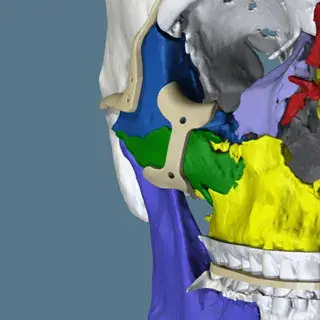

3D Systems' VSP® surgical planning solutions for craniomaxillofacial (CMF) applications received FDA clearance as a service-based approach to personalized surgery over 10 years ago.

3D Systems and Stryker Corporation have partnered to provide surgeons with best-in-class products and services for craniomaxillofacial surgeries. As a leader in personalized healthcare solutions, 3D Systems has planned and delivered devices for more than 140,000 patient-specific cases. The Stryker Craniomaxillofacial business specializes in providing patient-specific options and innovative solutions that help drive efficiencies in surgical suites. The combination of Stryker’s specialized team and advanced implants with 3D Systems' cutting-edge 3D printing technologies and expert consulting services positions both companies to provide a superior level of service to healthcare professionals who use these revolutionary solutions.